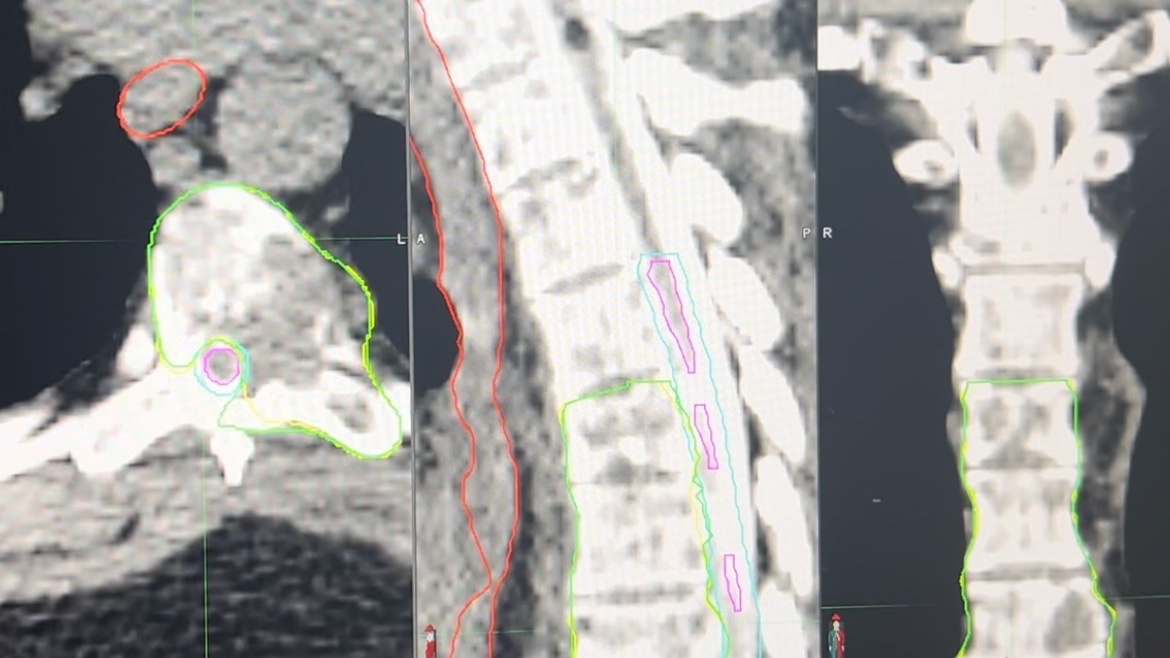

So I see a #lymphoma pt urgently with a large mass in the liver on 10/30/25. We submitted to @AnthemBCBS for authorization for palliative #XRT. They took their time and on 11/12/25, requested a 3D vs IMRT plan. We submitted it, knowing the extra dosimetry work would be done for…